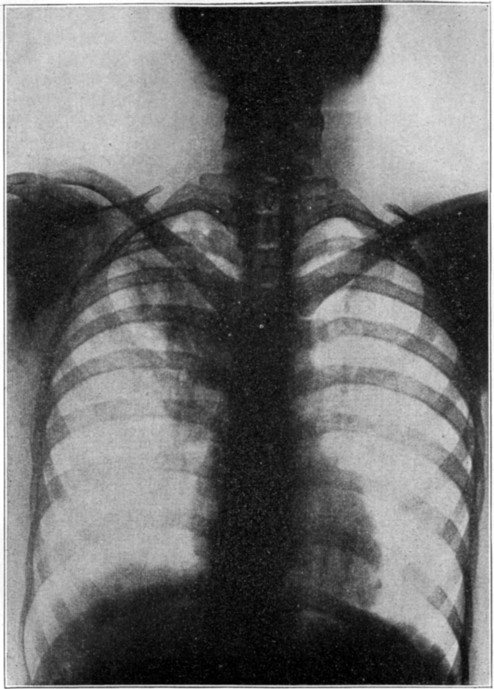

16X ray showing tuberculosis of the lung346